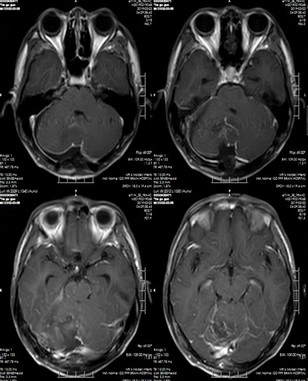

頭部MRI分析

術(shù)后MR示:1.右側(cè)小腦半球毛粘液性星形細(xì)胞瘤切除術(shù)后改變,原右側(cè)小腦半球病變已切除;2.四腦室受壓較前緩解,幕上腦室系統(tǒng)擴(kuò)張較前緩解,腦室旁間質(zhì)水腫范圍較前縮小。

專家點(diǎn)評(píng):毛粘液性星形細(xì)胞瘤是發(fā)生于神經(jīng)系統(tǒng)的,粘液樣結(jié)構(gòu)的毛細(xì)胞星形細(xì)胞來源腫瘤,生物學(xué)特征具有侵襲性,相比于一般毛細(xì)胞星形細(xì)胞瘤易復(fù)發(fā),多見于兒童、青少年,男性多見,多發(fā)生于下丘腦/視交叉,也可見于小腦、側(cè)腦室、第三腦室、基底節(jié)等部位,癥狀取決于腫瘤生長(zhǎng)部位及大小,多為占位效應(yīng)引起的相關(guān)癥狀。手術(shù)切除是本病的主要治療手段,手術(shù)切除腫瘤可以減輕患者癥狀,同時(shí)可明確腫瘤病理,可顯著延長(zhǎng)患者的生存期,提高患者生活質(zhì)量。